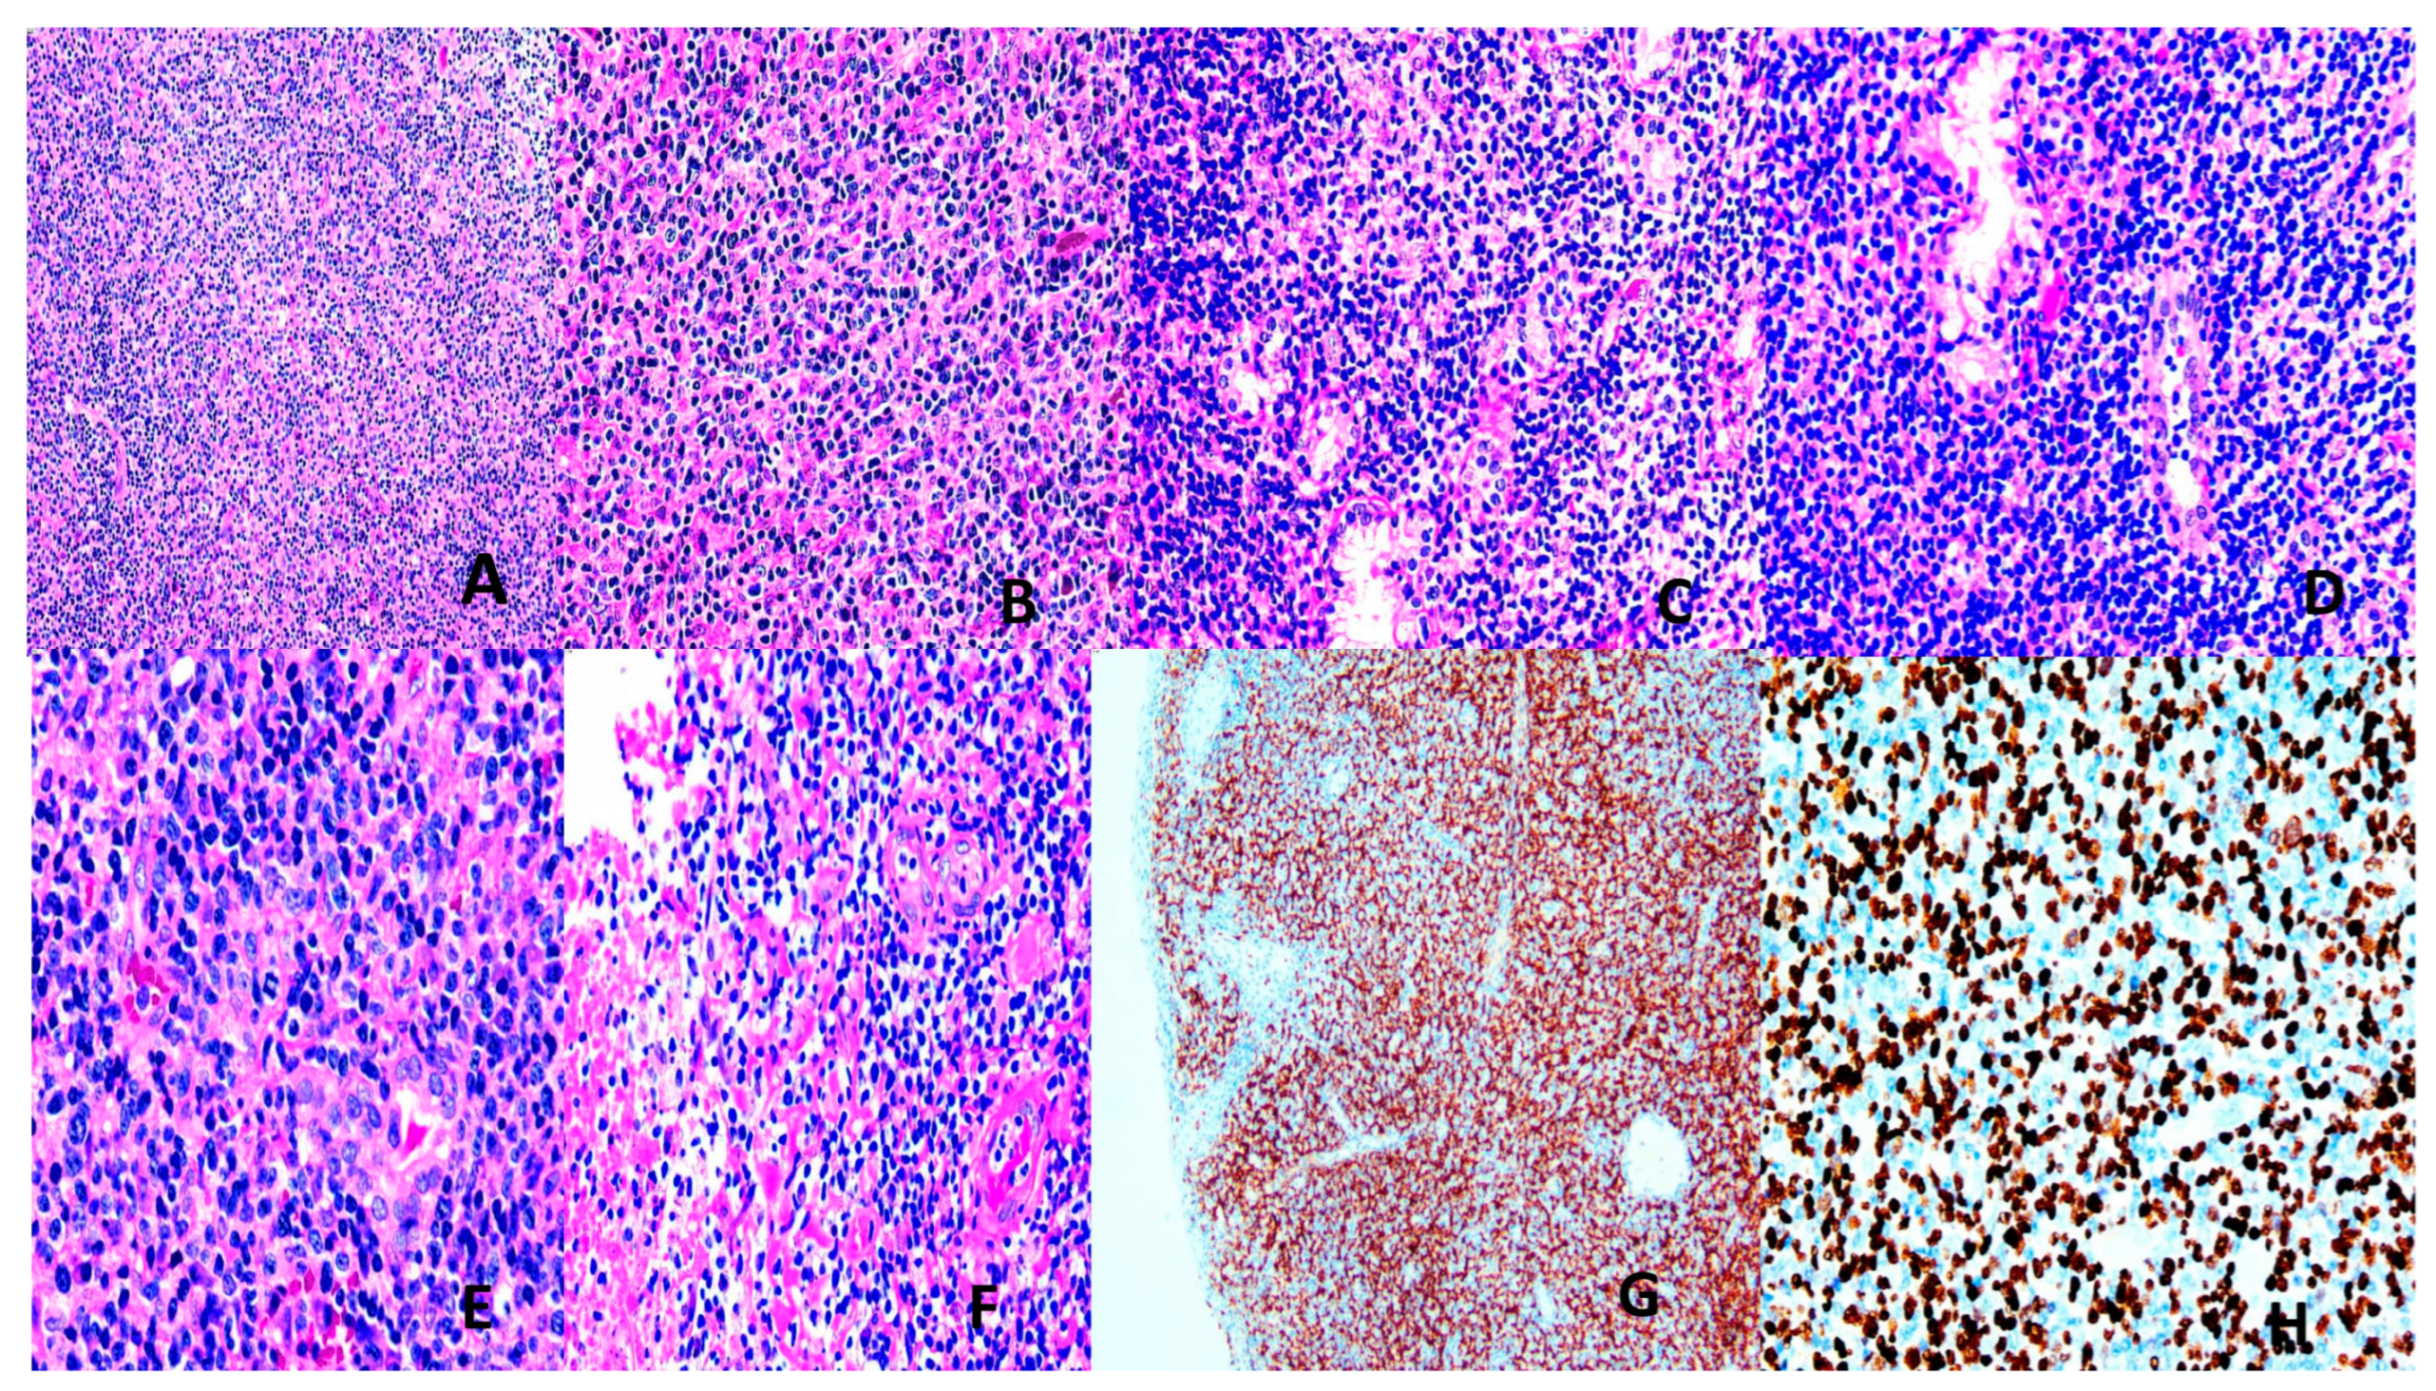

Extranodal NK/T-Cell Lymphoma (ENNKTL)

Most (60–90%) ENNKTL are derived from NK cells, and the remaining 10–40% from T-cells [7,137]. Eighty percent are nasal and 20% non-nasal. Nasal NNKTL presents with midfacial disfiguring, destructive lesions of the upper aerodigestive tract, and affects males in the 4th to 5th decades. It is histologically characterized by diffuse sheets of atypical lymphoid cells, usually with a broad range of sizes and irregular nuclei. Epithelial invasion, angiocentricity, angioinvasion, and extensive geographical necrosis are typical features. The NK-cell type is negative for surface CD3, T-cell receptor (TCR), and positive for CD56 with no TCR rearrangement. The T-cell type is surface CD3+, TCR+ with rearranged TCR. There is frequent cytotoxic molecule expression (Figure 4). A strong etiologic relationship with EBV (latency 2) is present [7,133,137]. A multitude of alterations in genes encoding proteins of the JAK/STAT and NF-KB pathways and epigenetic changes, including dysregulated microRNA, tumor suppressor genes, myc overexpression, and effects of EBV latency products (LMP1 contributes to immune evasion) are operative [7,133,137]. Treatment involves concurrent or sequential chemoradiotherapy using L-asparaginase-containing non-anthracycline regimes. Immune checkpoint inhibitors and stem cell transplantation may be required [7,133,138]. Plasma EBV DMA level is an indicator of chemosensitivity and prognosis [7,133,139].